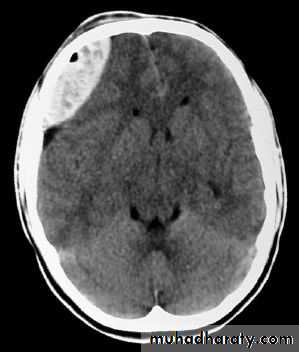

1. Brain Oedema (Cerebral Swelling)

Can be local (around a haematoma) or diffuse.

It is due to intracellular or extracellular accumulation of fluid.

It leads to raised intracranial pressure, which itself causes problems.

It is more common and more dangerous in children.